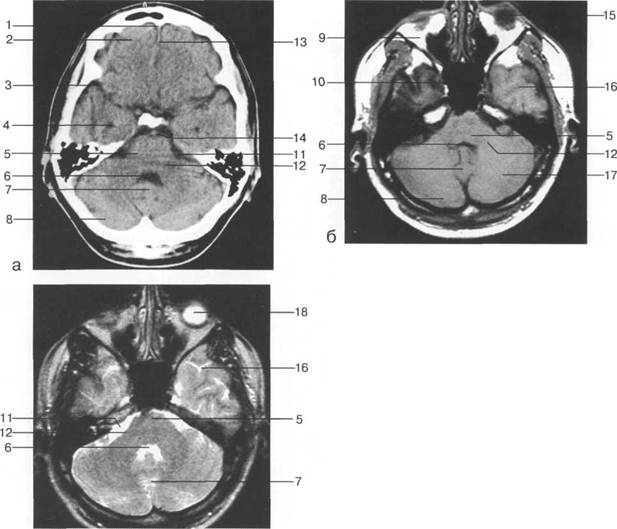

рога боковых желудочков; б - через структуры задней череп 13513u2010n 85;ой ямки.

Задняя череп 13513u2010n 85;ая ямка представляет собой часть основания череп 13513u2010n 72;, ограниченную централь

Следует отметить, что в настоящее время оптимальным методом исследования структур задней череп 13513u2010n 85;ой ямки является МРТ, которая, в отличие от КТ, лишена артефактов от кост

Мозжечок заполняет практически весь объем задней череп 13513u2010n 85;ой ямки. Его поперечный раз

височная доля; 17 - полушарие мозжечка; 18 - |

Следует остановиться на анатомии подпаутинных пространств задней череп 13513u2010n 85;ой ямки IV 20 мм. Между основанием череп 13513u2010n 72; и нижней поверхностью мозга от большого затылочного отверстия вдоль ската и спинки турецкого седла простирается задняя базальная цистерна. В зави IV